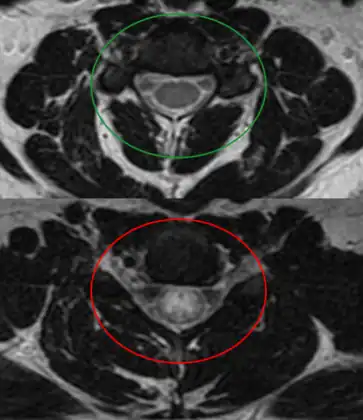

MRI of individual diagnosed with transverse myelitis

Axial T2 MRI of cervical spine demonstrating normal cord signal (green circle) and increased T2 signal in the central cord (red circle).